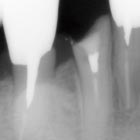

Nd:YAGレーザーによる

幅広い臨床治療例

【臨床治療例】

●乳歯萌出困難に対する歯肉開窓術 ●ホワイトニング ●止血効果、歯肉の接合、 創傷治癒の促進 ●メタルコア除去 ●創 傷治癒促進、疼痛緩和